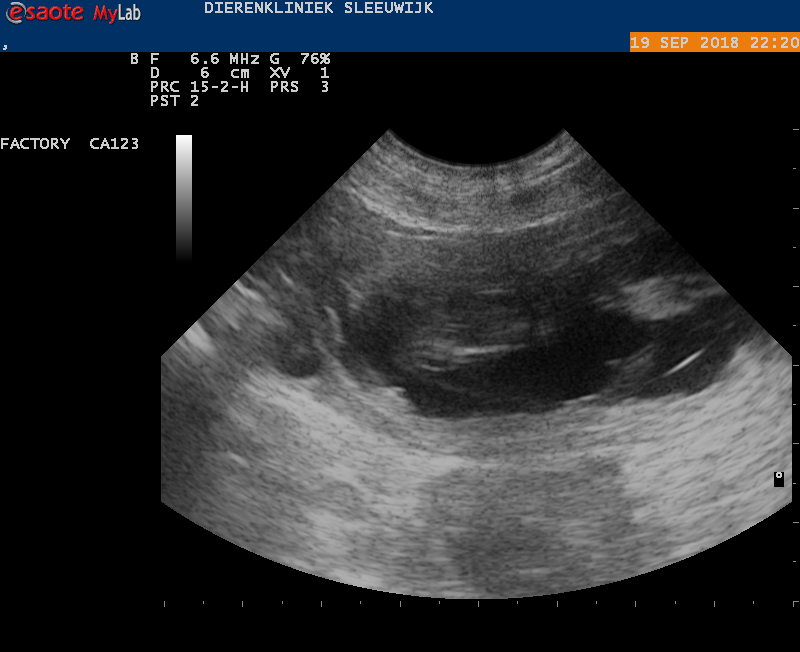

De echo van 20 september 2018